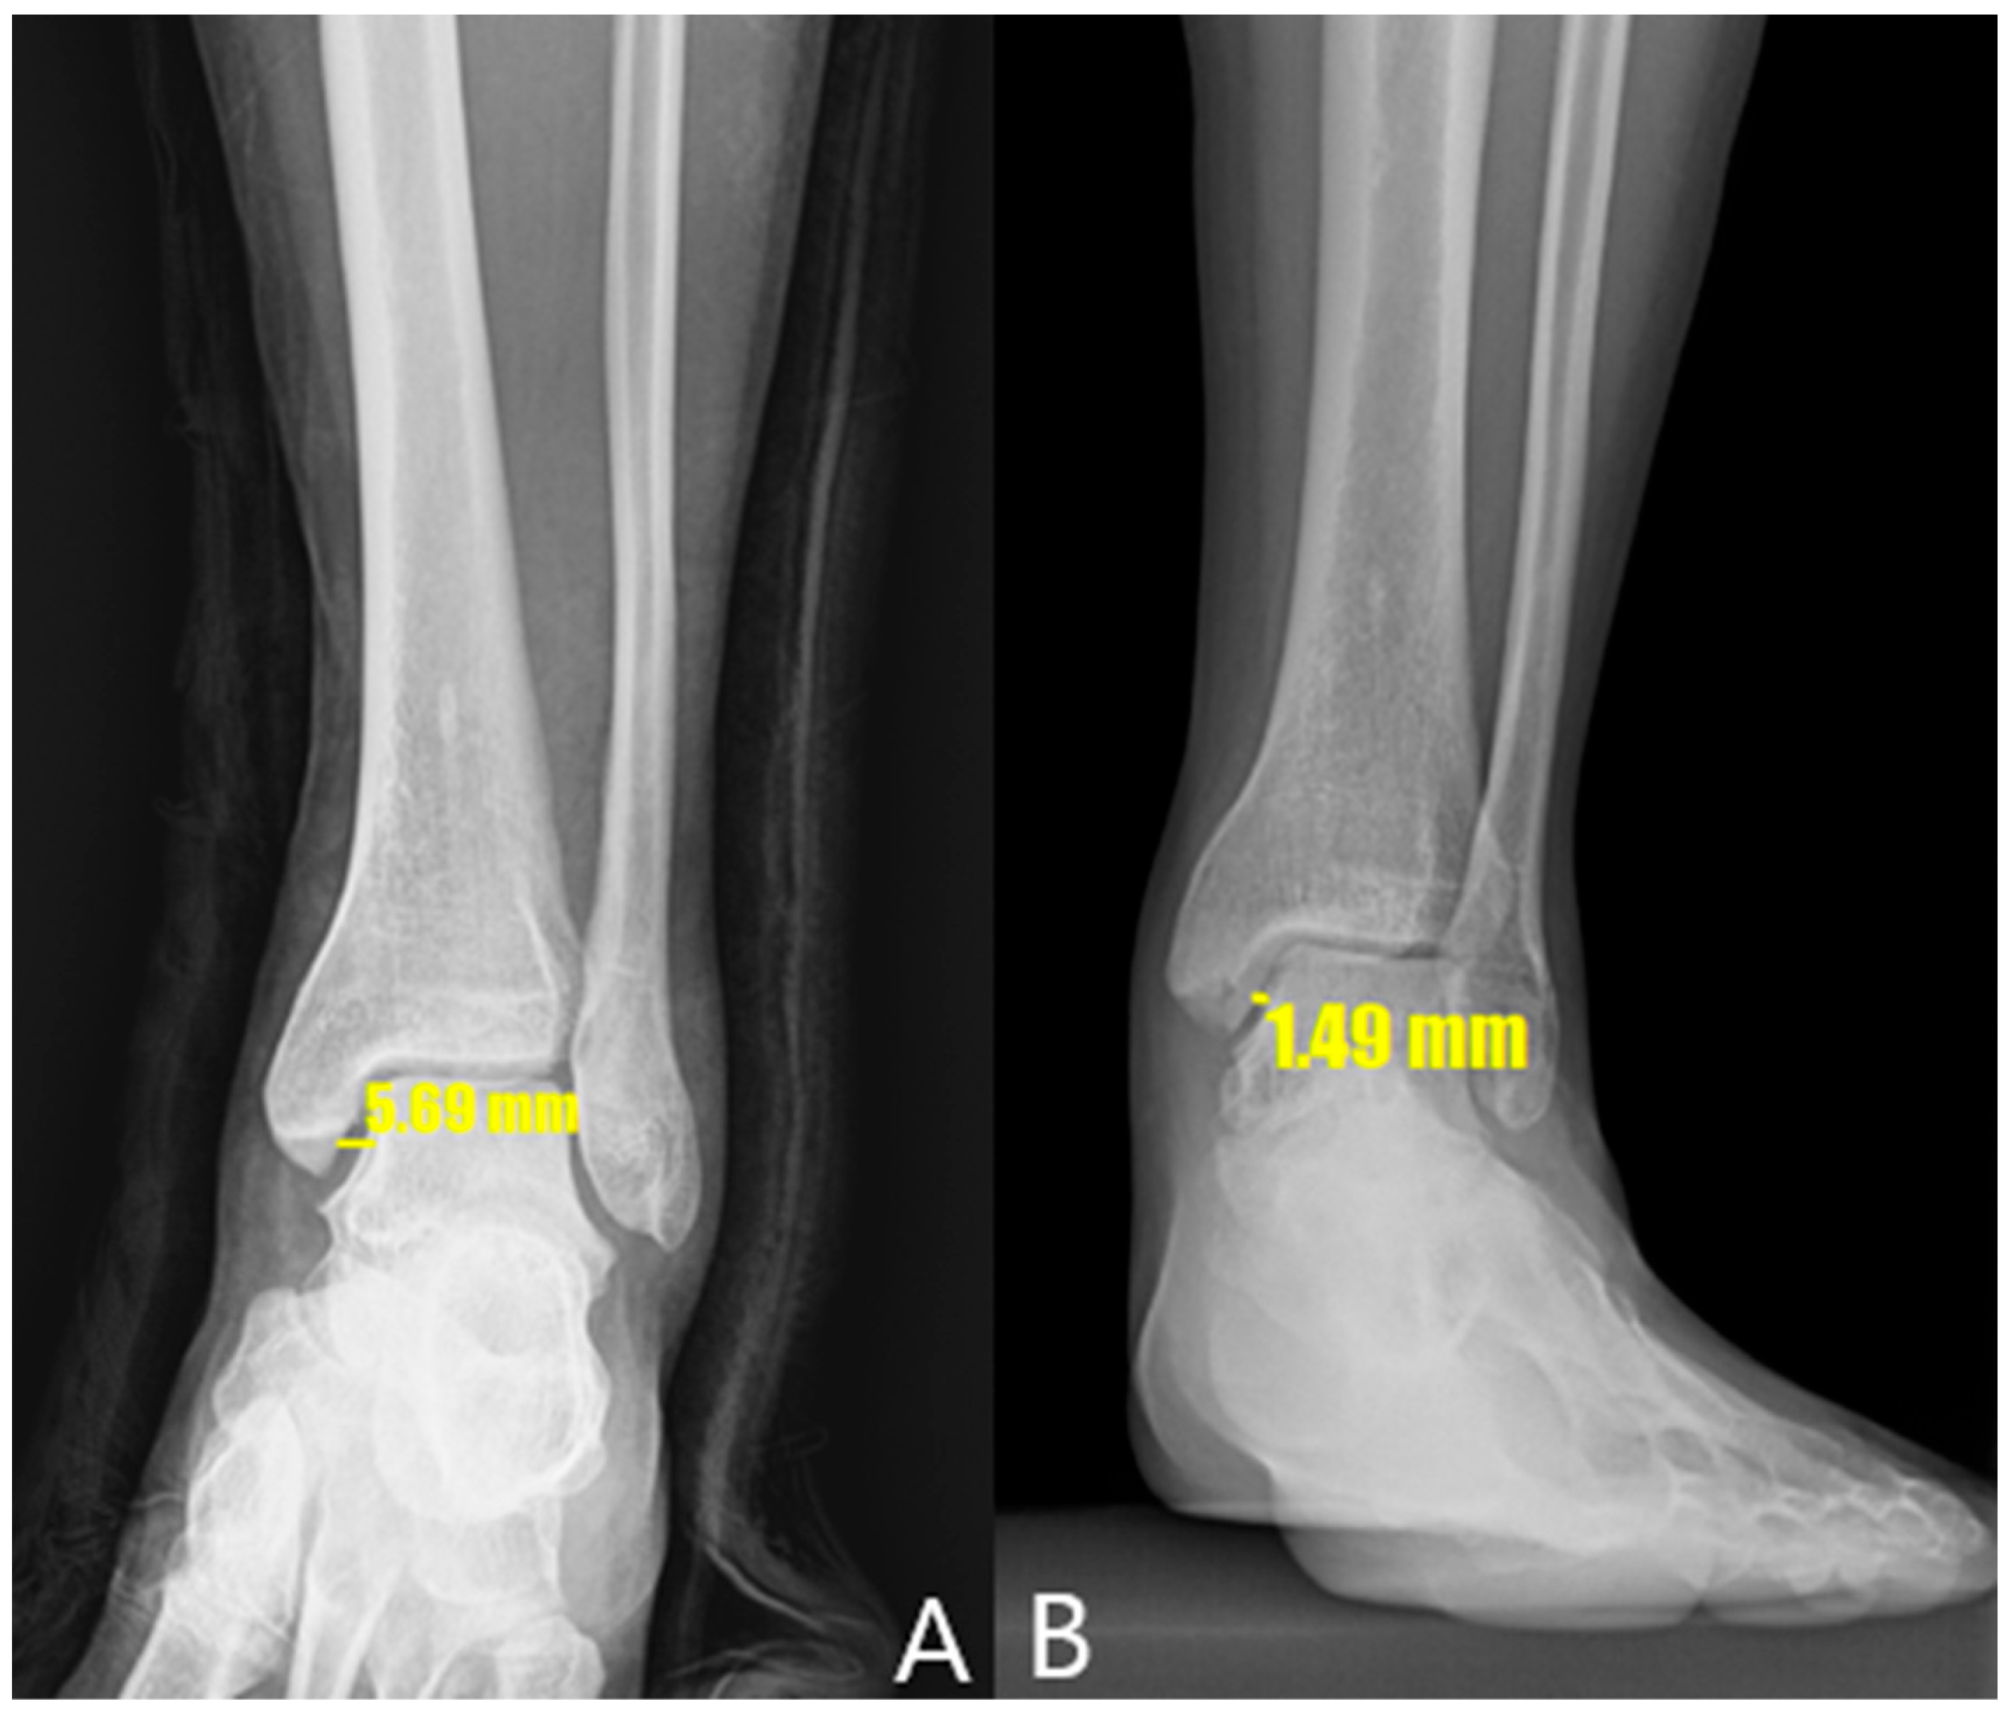

Table 3 compares the radiological outcomes between the two groups. The preoperative MCS values in the arthroscopic and open repair groups were 3.1 mm and 6.56 mm, respectively. The immediate postoperative MCS values in the arthroscopic and open repair groups were 2.2 mm and 2.53 mm, respectively. The median MCS values after 1 year in the arthroscopic and open repair groups were 2.21 mm and 2.24 mm, respectively. The median MCS values measured by stress radiography at 1 year in the arthroscopic and open repair groups were 2.62 mm and 3.07 mm, respectively. These findings indicate significant differences in the preoperative, immediate postoperative, and 1-year postoperative MCS values between the groups, while no significant differences were detected in the postoperative MCS values at 6 months or 1 year. Additionally, the MCS values measured by stress radiography at both 6 months and 1 year significantly differed between the two groups. However, the improvement in MCS values before and after surgery in both groups means that the radiological results after surgery were better than before surgery for both methods. In Figure 4, an X-ray of one of the patients who participated in this study shows that MCS value had improved after surgery.

Figure 4. X-ray of one patient who participated in this study. (A) MCS value before surgery. (B) MCS value has improved 1 year after surgery.